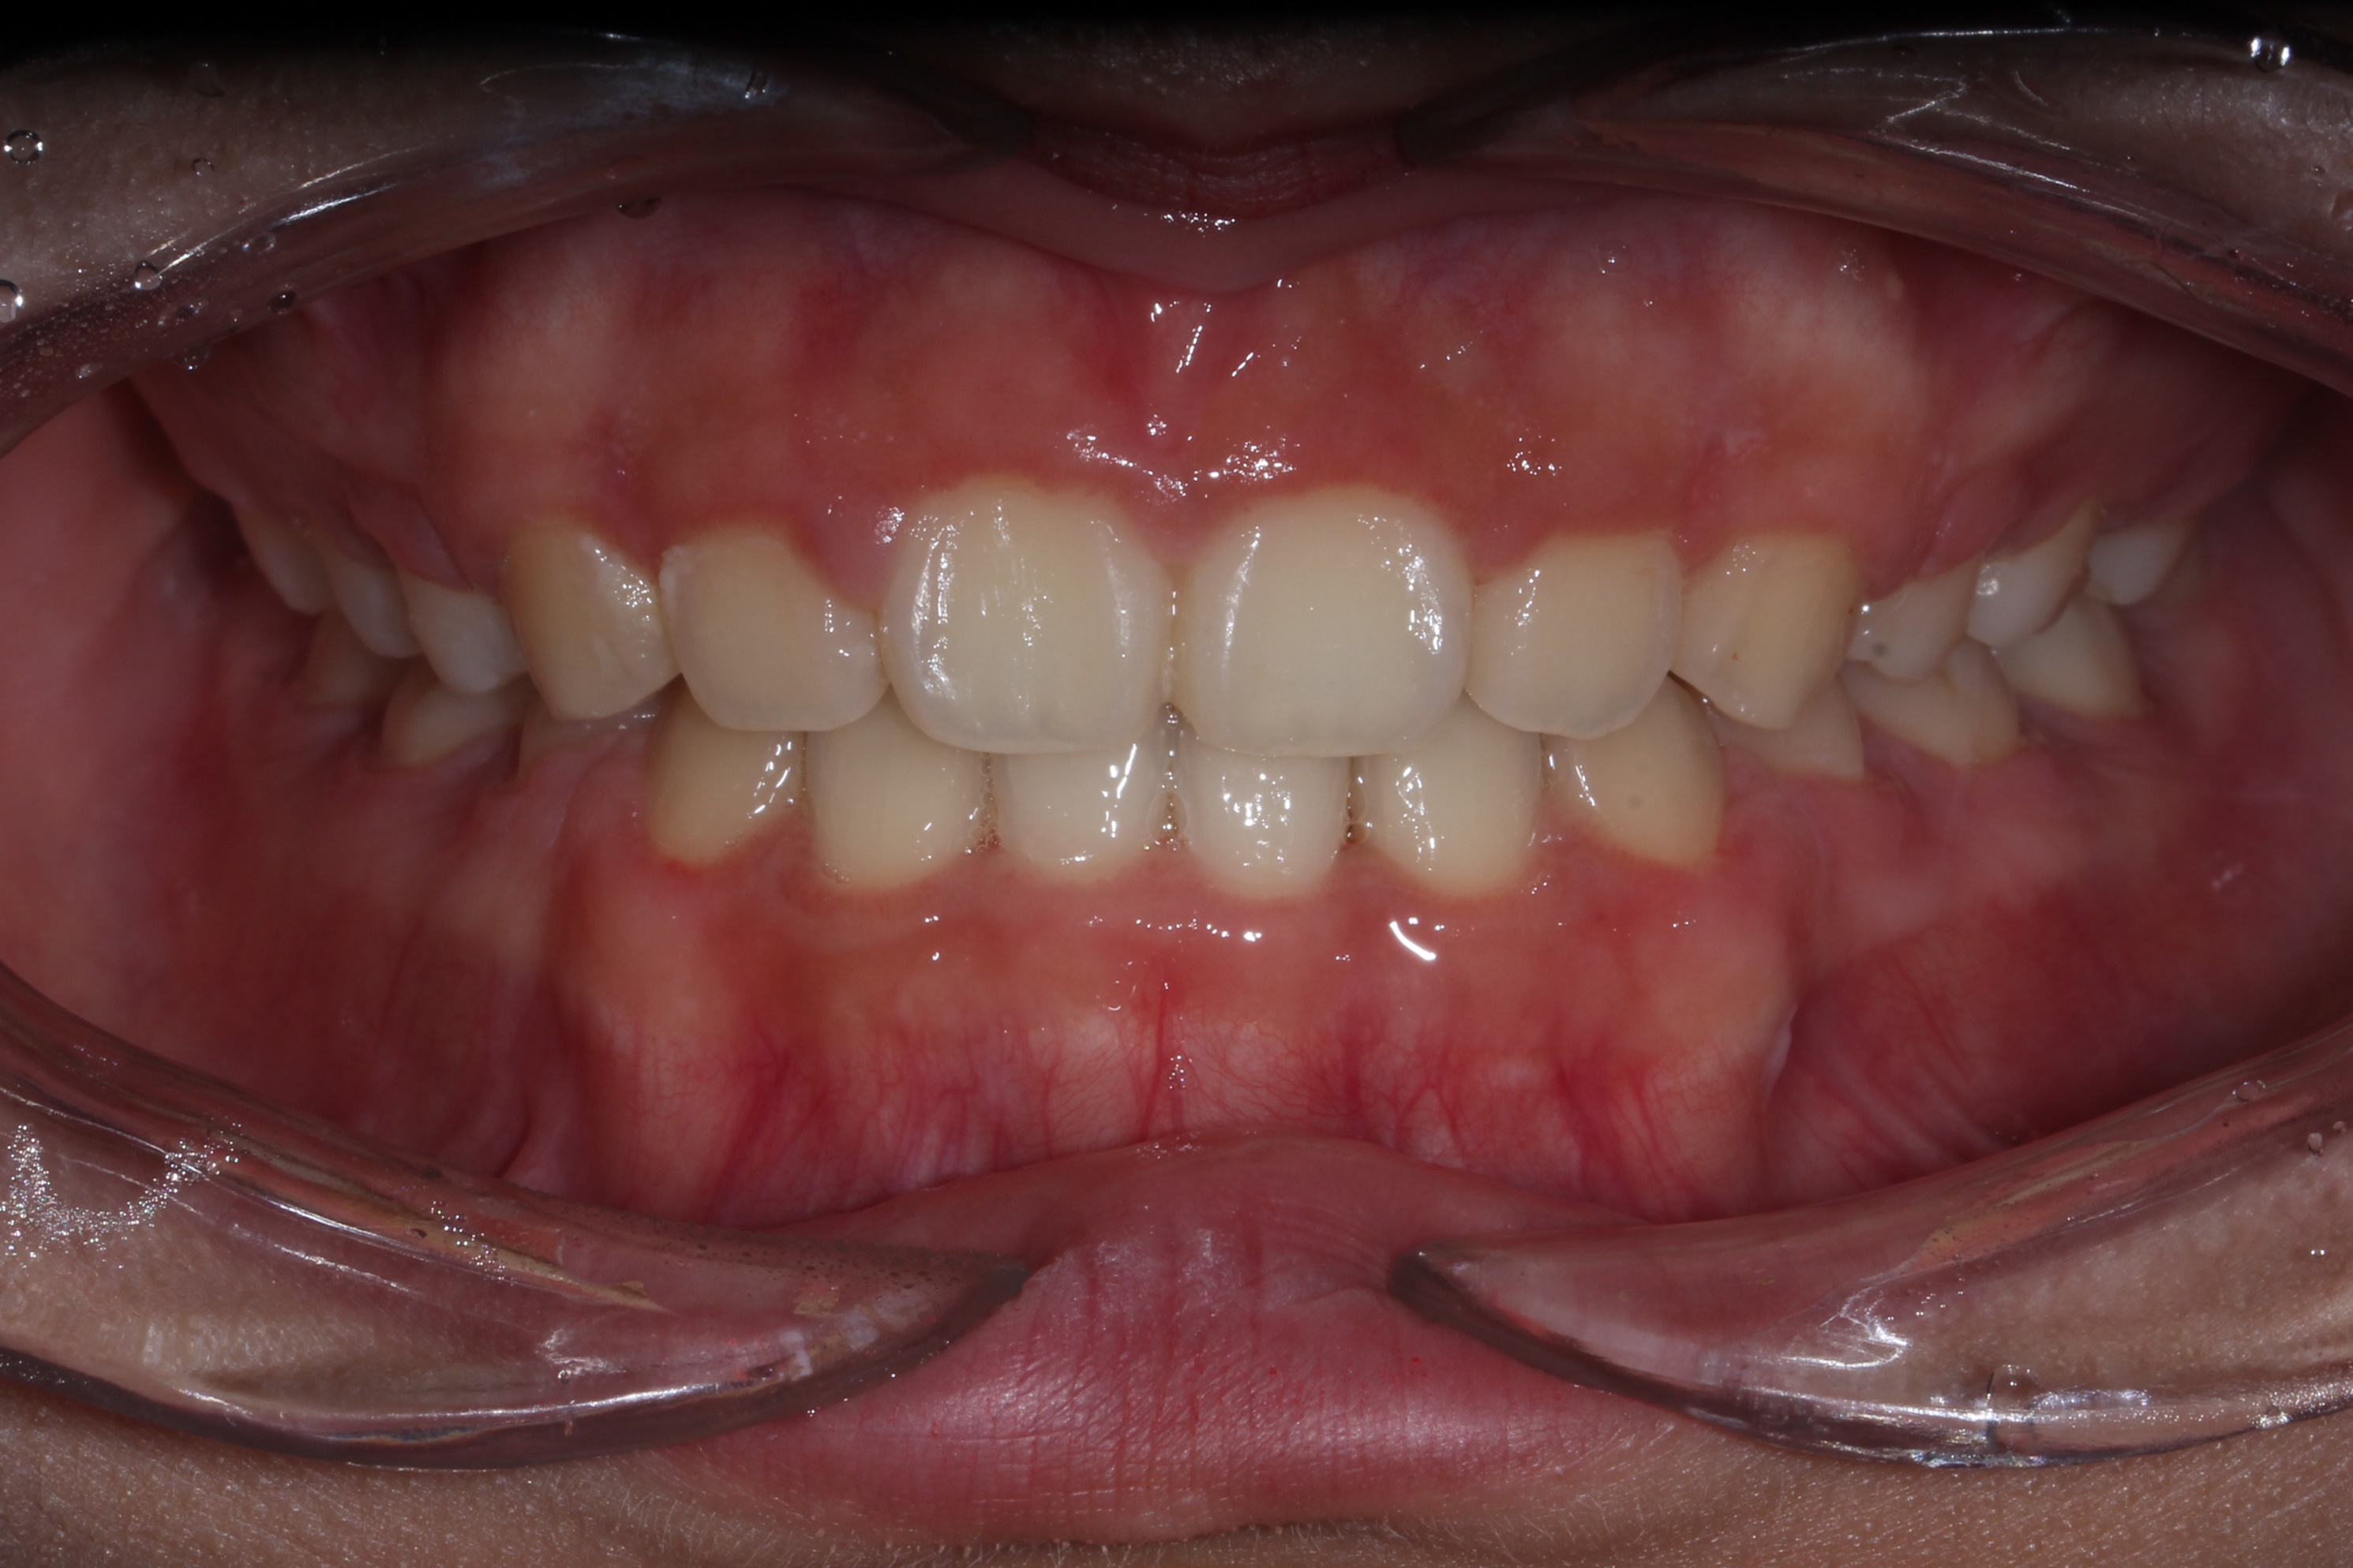

돌출입의 경우 입술의 두께, 앞니의 각도, 후방이동시켜야 하는 양 등을 종합적으로 고려하여 발치 유무를 결정합니다.

위 케이스에서는 발치교정을 이용하여 치아를 후방이동시켜 돌출입을 해소하였습니다.

총 교정기간은 18개월입니다.